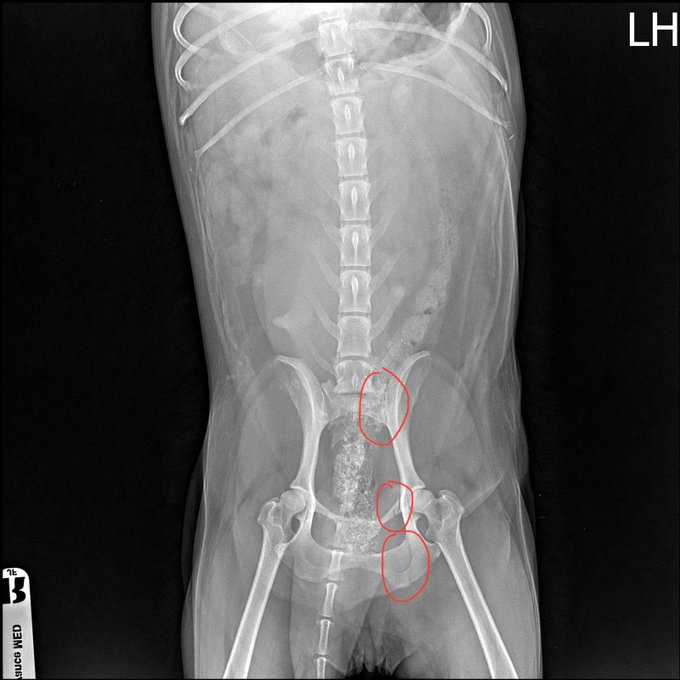

🦴 Her bacakları ve kalçası kırılmıştı.

Ayrıca karnında tümörler vardı.

İlk ameliyat başarısız oldu. Bacağı o kadar kötüydü ki plaka ve vida takılması gerekti. Ancak enfekte oldu ve başarısız oldu.